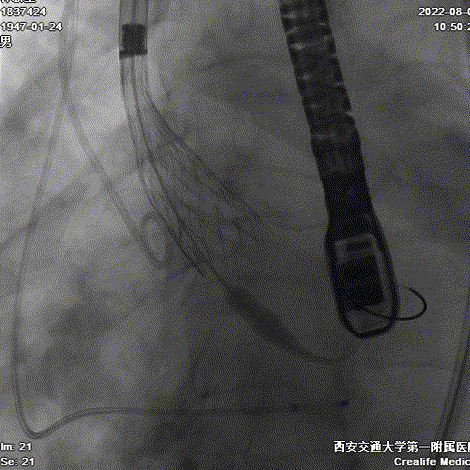

Type0型二叶瓣伴偏心性钙化导致瓣膜定位困难,如果释放位置偏浅,瓣膜蹦出风险高。术者利用Evolut PRO稳定的多次可回收功能,通过调整瓣膜植入深度,确保瓣膜流入端稳固锚定在瓣环根部。通过造影评估,瓣膜植入位置理想,因此进行过最后缓慢释放,瓣膜顺利达到目标植入深度。

首次释放

二次释放

评估

最终释放